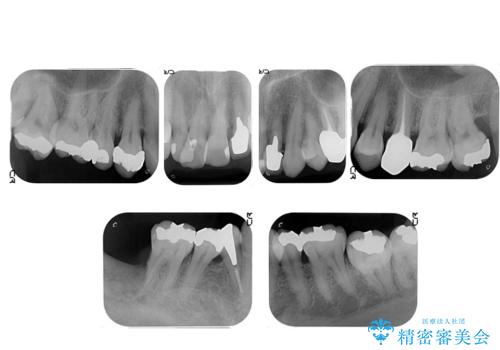

- 歯周病を気にして来院。

前歯の虫歯を治そうにも、歯並びの問題で難しい状態でした。

右下の奥歯も欠損しており、インプラント治療が必要な状態でした。

前歯の部分矯正を行い受け口を改善しました。

奥歯まで動かそうとすると顎の手術の適応になってしまうため、奥歯はそのままにして前歯のかみ合わせを改善しました。

また、奥歯はインプラント治療を行い、矯正で下の前歯を後ろに下げるのに使用しています。

前歯が重なっているところの虫歯治療が難しく、そこから矯正治療の提案となりました。

下の前歯1本、また、左上2番を保存不可能なため抜歯しています。

通常骨格的な受け口を部分矯正でというのは不可能なことが多いのですが、今回はいろいろな条件が重ねなりお引き受け可能でした。通常は難しいです。